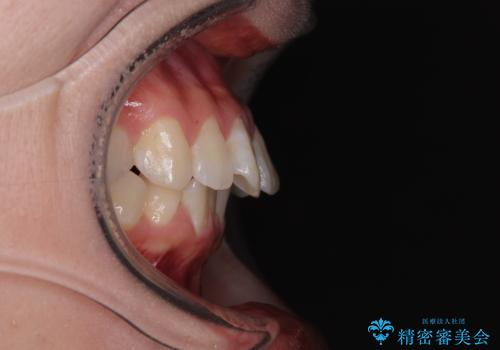

深い咬み合わせによる隙間 インビザライン矯正でコンプレックスを改善

- 上の前歯の隙間を気にして来院された患者様です。

インビザラインにより、上下の歯列を側方に拡大しつつ、前歯の隙間を閉じていくこととしました。

隙間の原因は強い咬合力や舌の突出癖、小帯の異常付着などがありますが、舌のトレーニングをしっかりと行いながら、装着時間を遵守して装着していただいたおかげで、スムーズに治療を終えることができました。